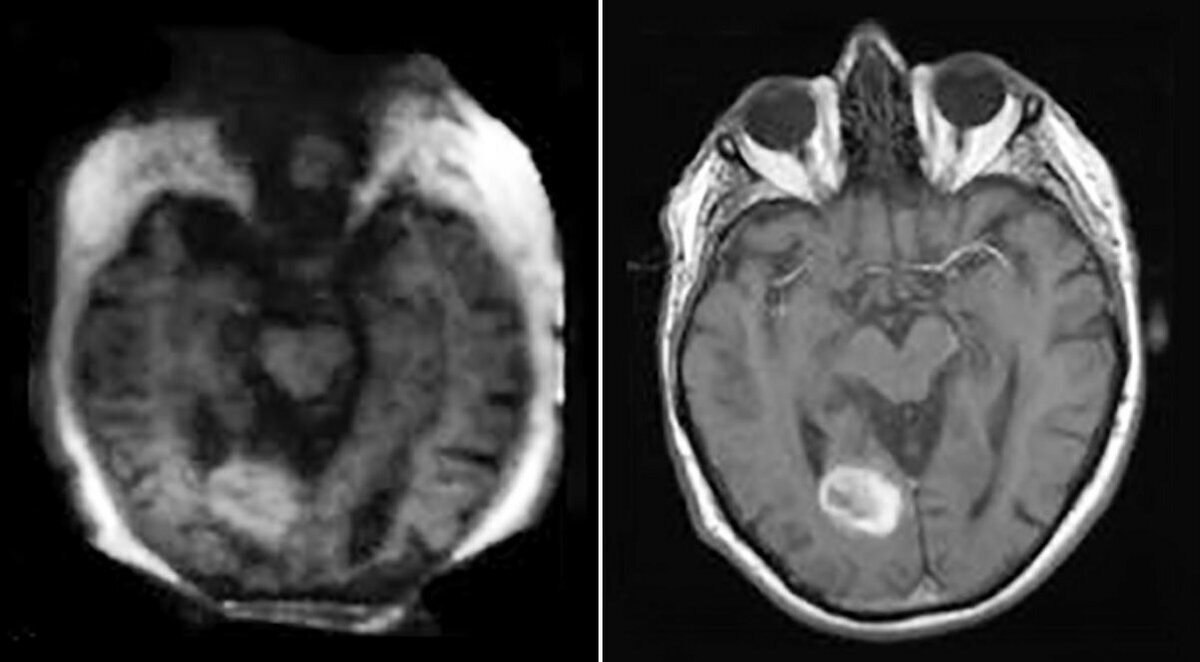

Разрешение сканирования мозга с помощью низкопольного аппарата (первое изображение) более грубое, чем у обычной МРТ (второе изображение), но на обоих изображениях четко видно кровоизлияние.